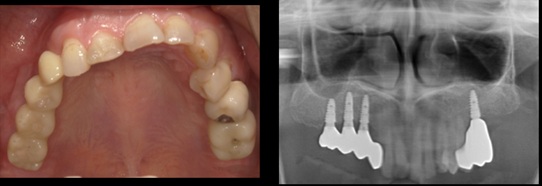

無歯顎に骨造成を行いインプラント埋入(60代女性)

治療前

治療後

施術名 | GBR,ソーセージテクニックTIメッシュ ソケットリフトFGG |

主訴 | ほかの医院で入れたインプラントがすべて取れたので噛めない |

施術の副作用(リスク) | 感染脱落 |

施術の価格 | 1本GBR5万~10万(税抜き)+インプラント埋入補綴まで35万(税抜き) |

コメント | 骨がなくなっていたのでしっかり作ってからインプラント埋入を行いました |